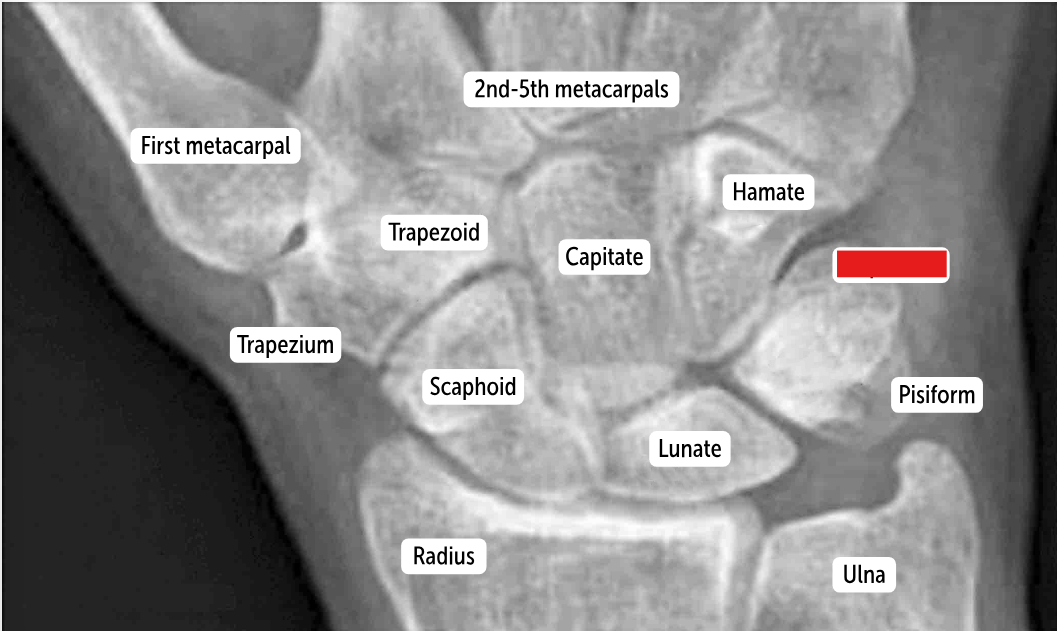

The most commonly fractured carpal bone by falling on an outstretched hand, which has a risk of avascular necrosis, is the __________.

Scaphoid bone

The most commonly dislocated bone after a fall on an outstretched hand is the ___________.

Lunate bone

Carpal bones by row:

So Long To Pinky, Here Comes The Thumb

Scaphoid, Lunate, Triquetrum, Pisiform, Hamate, Capitate, Trapezoid, Trapezium

Scaphoid

Lunate

Triquetrum

Pisiform

Hamate

Capitate

Trapezoid

Trapezium

The two distinct rows articulate with each other at the __________. It’s a plane (simple sliding) joint that acts to amplify all the other wrist actions.

midcarpal joint

Which carpal bones articulate with the metacarpal bones?

The bones of the distal row (hamate, capitate, trapezoid, and trapezium) articulate with the metacarpal bones.

The true wrist joint is better called the radio-carpal joint. It is an __________ formed by the articulation of the distal radius and its articular disk to the scaphoid and lunate bones in the first row of carpals.__________ can move in two dimensions.

(Both are the same term)

Ellipsoidal joints